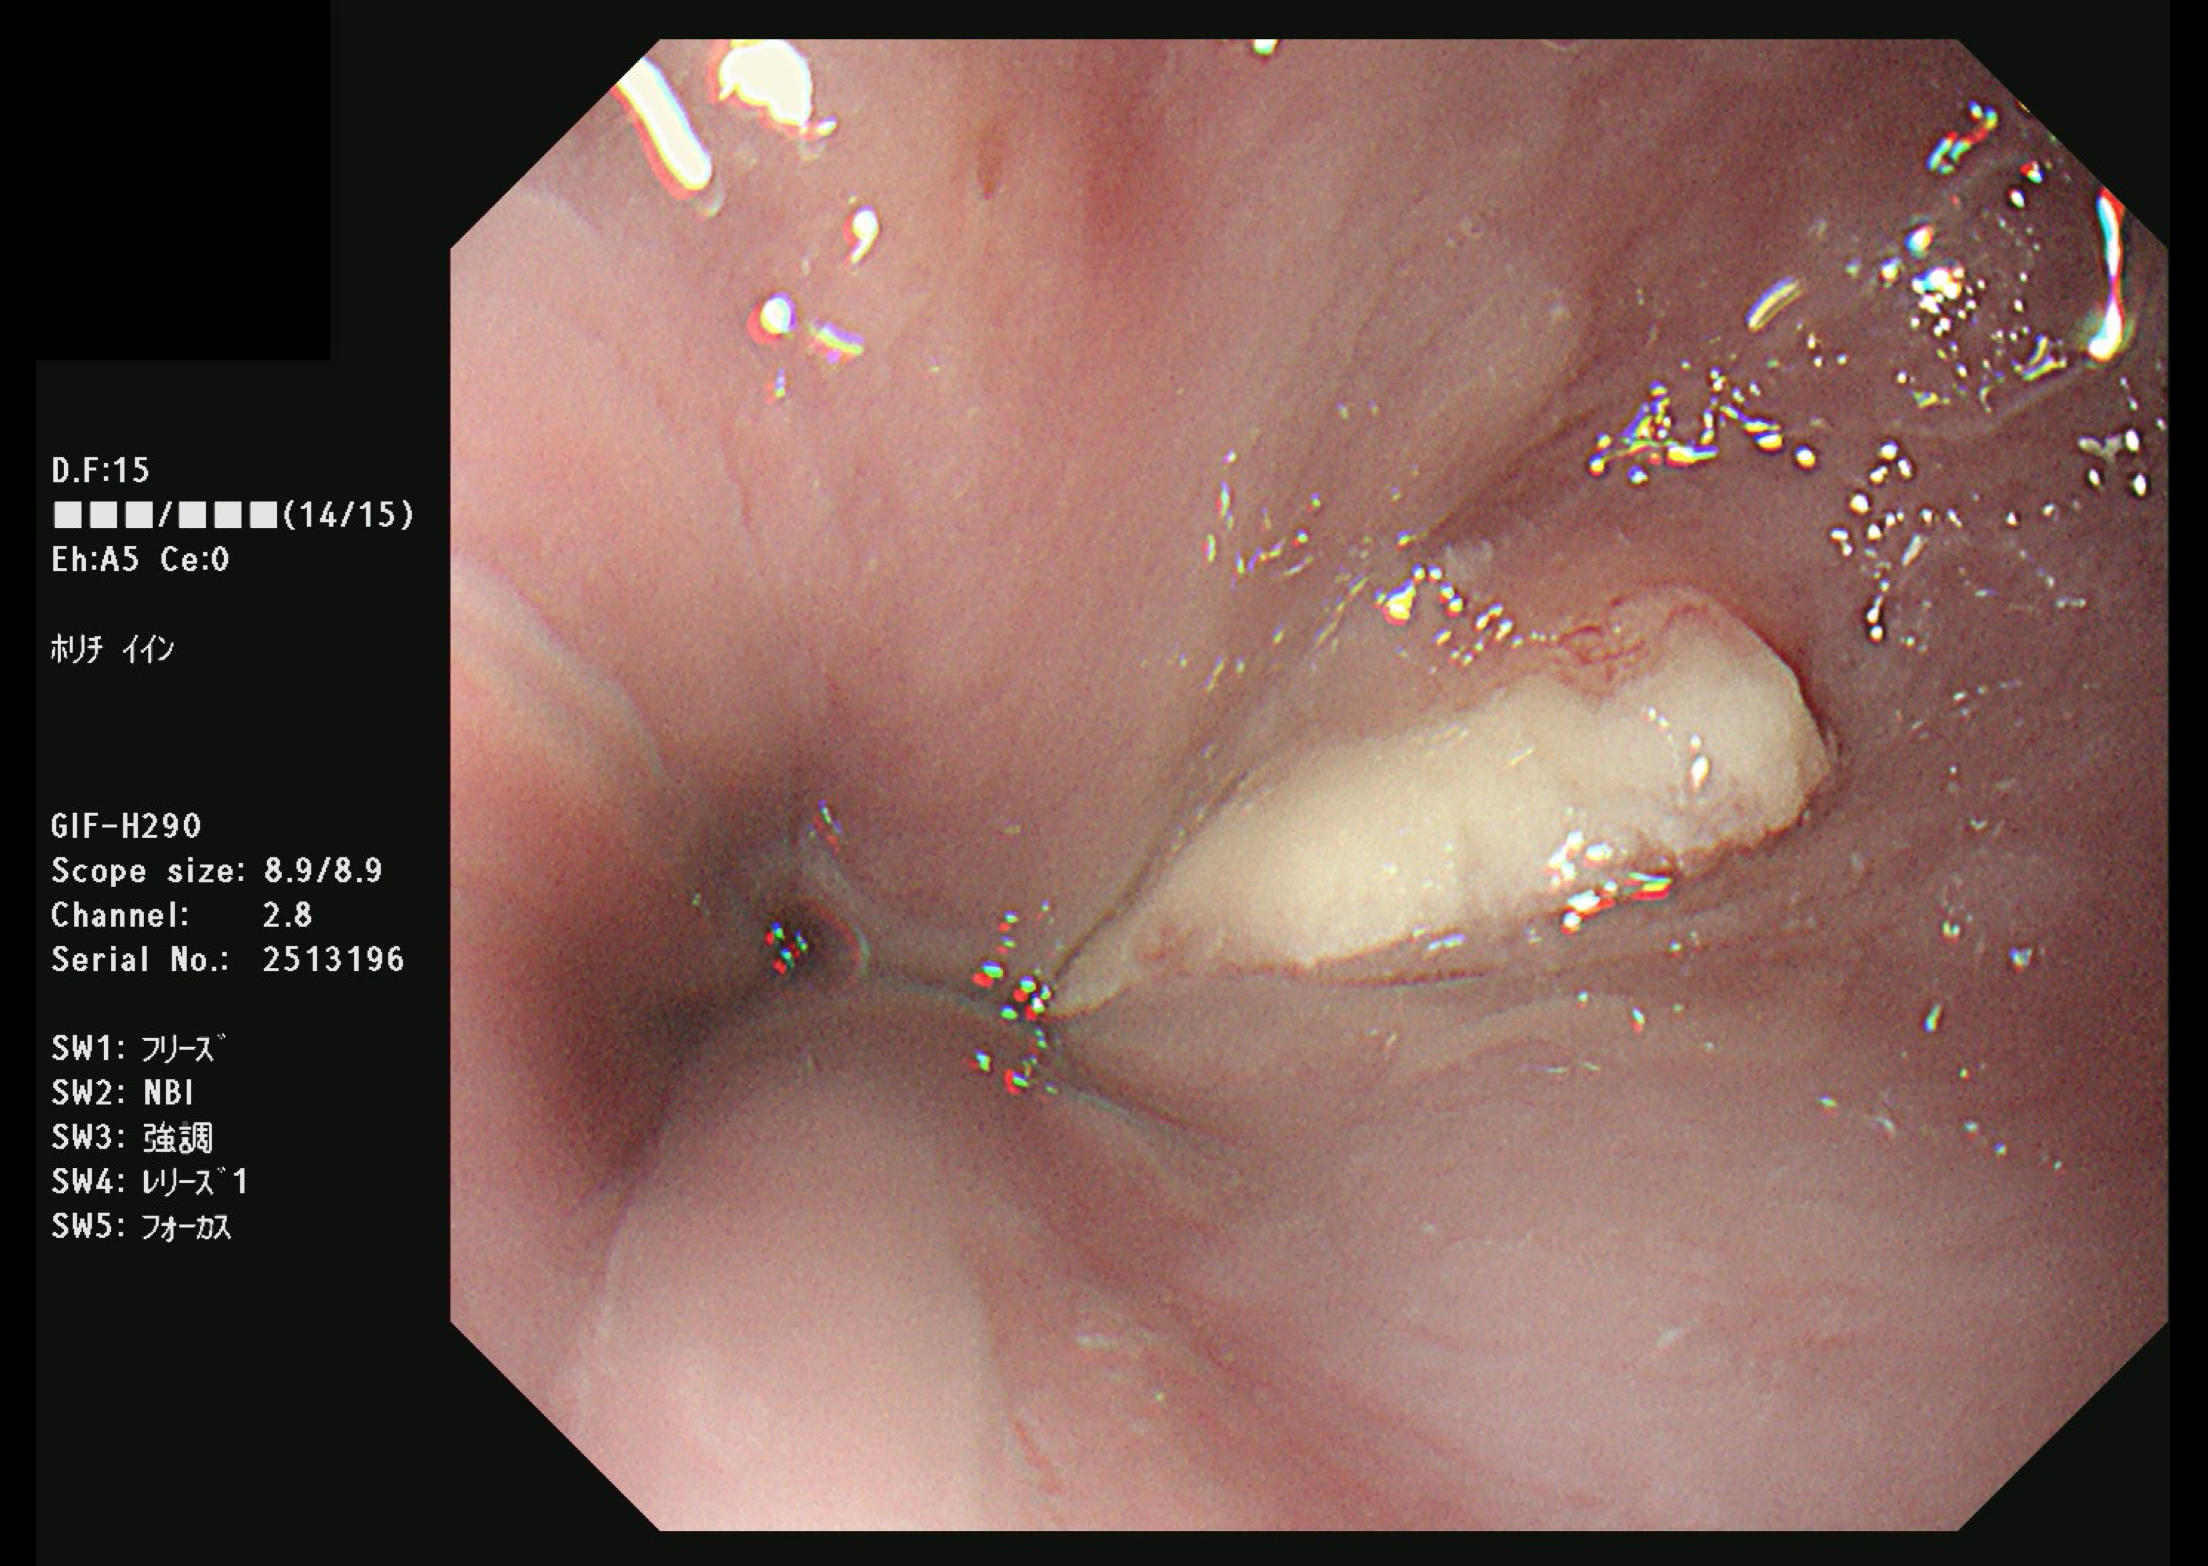

食道がん(上部消化管内視鏡)

胃がん検診では喉頭部・食道・十二指腸上部を観察します。

当院では胃内視鏡(経口)のみを実施しております。胃の中を十分に検査するために高解像度の内視鏡を使用しており、そのため口からの内視鏡検査となります。一般的に鼻からの経鼻内視鏡による検査の方が楽な検査と言われていますが、内視鏡が細い分、最新型の経口高解像度内視鏡に比べて解像度が落ちます。